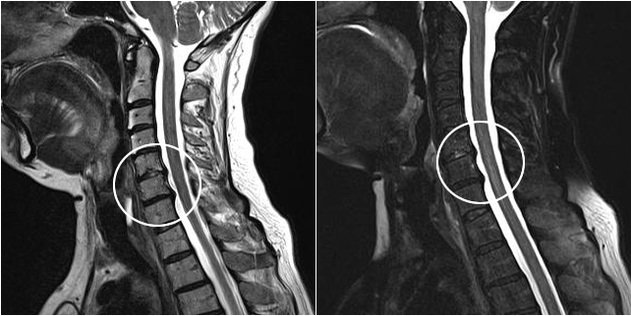

Modern diagnostic methods include MRI and CT, which allow the most accurate examination of the process of destruction of cartilage and bone tissue.Also, this technique is suitable for diagnosing hernias and other soft tissue defects near the source of the disease.

Cervical osteochondrosis

The first manifestation of cervical osteochondrosis is a headache.Analgesics do not relieve pain.Typically, the pain begins in the parietal zone, smoothly flowing into the temporal region.Over time, the patient begins to feel discomfort and numbness in the shoulder girdle.

Due to disturbed blood supply to the brain, a person may experience dizziness, nausea and increasingly severe tinnitus.If the nutrition of the optic zone is disturbed, then visual acuity usually decreases sharply.